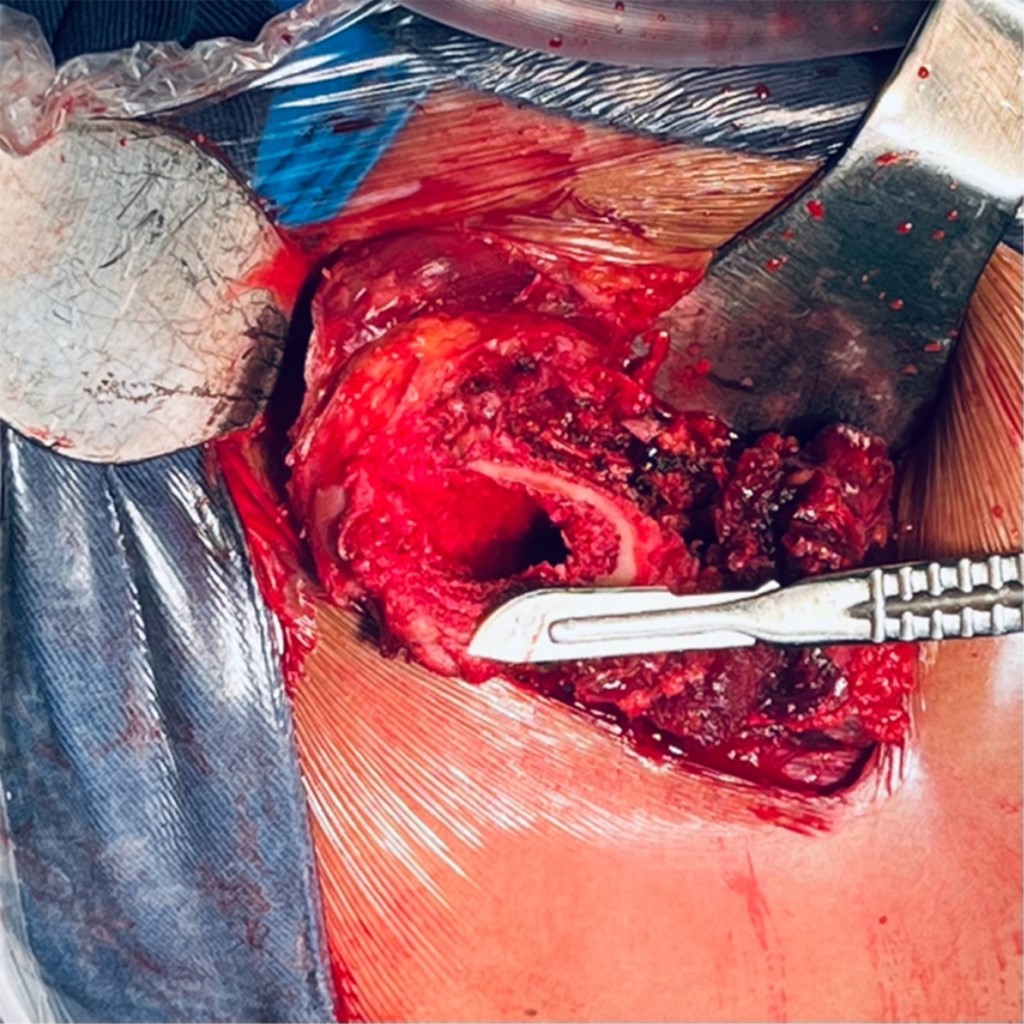

Con la paciente bajo anestesia regional y previa profilaxis antibiótica, se coloca en posición de cubito lateral derecho. Por anatomía de superficie se identifican referencias anatómicas: trocánter mayor y diáfisis femoral. Se realiza un abordaje lateral directo de Hardinge, disección por planos aplicando hemostasia con electrocauterio, se hace un corte longitudinal de fascia lata con tijera de Metzenbaum; se efectúa colgajo muscular de glúteo medio y menor (Figura 2); posterior a esto, capsulotomía en T invertida, para identificar cabeza femoral y realizar osteotomía a 10 mm por arriba del trocánter menor; se identifica ligamento redondo (Figura 3), con el fin de diseccionar hasta su origen sobre la escotadura y localizar el acetábulo nativo, retirando tejido blando remanente de cápsula articular (Figura 4).

Figura 2